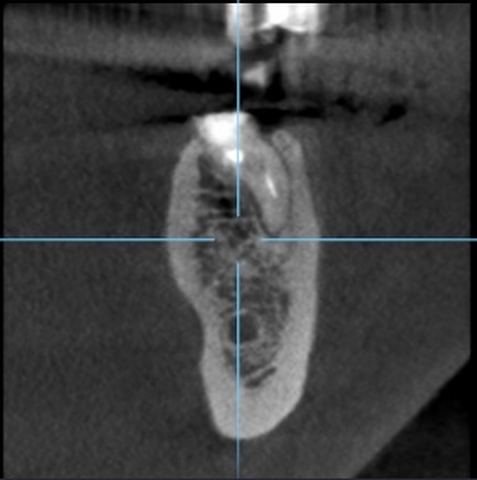

Ryc. 6. Przekrój zęba 36 w płaszczyźnie horyzontalnej.

Diagnostykę poszerzono o badanie tomografii wiązki stożkowej (ryc. 4-6). Region implantacji zwymiarowano w trzech płaszczyznach w specjalnym programie komputerowym 3Shape Implant Studio® (3Shape, Kopenhaga, Dania), wykonano szablon implantologiczny i przystąpiono do procedury chirurgicznej. Zaprojektowano użycie wszczepu o wymiarach 4,2 x 10 mm.